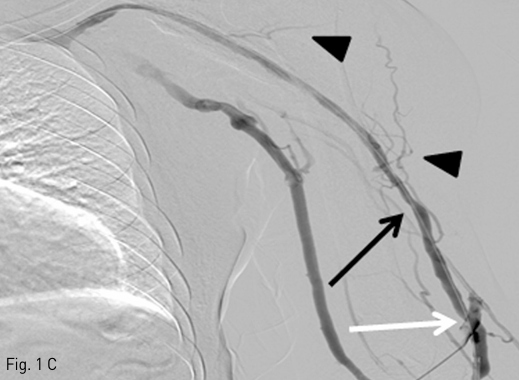

Fig 1C

C. A venography after balloon dilatation shows a graft to vein fistula (white arrow), and residual stenosis in cephalic vein (black arrow), and collateral vessels (arrowheads).